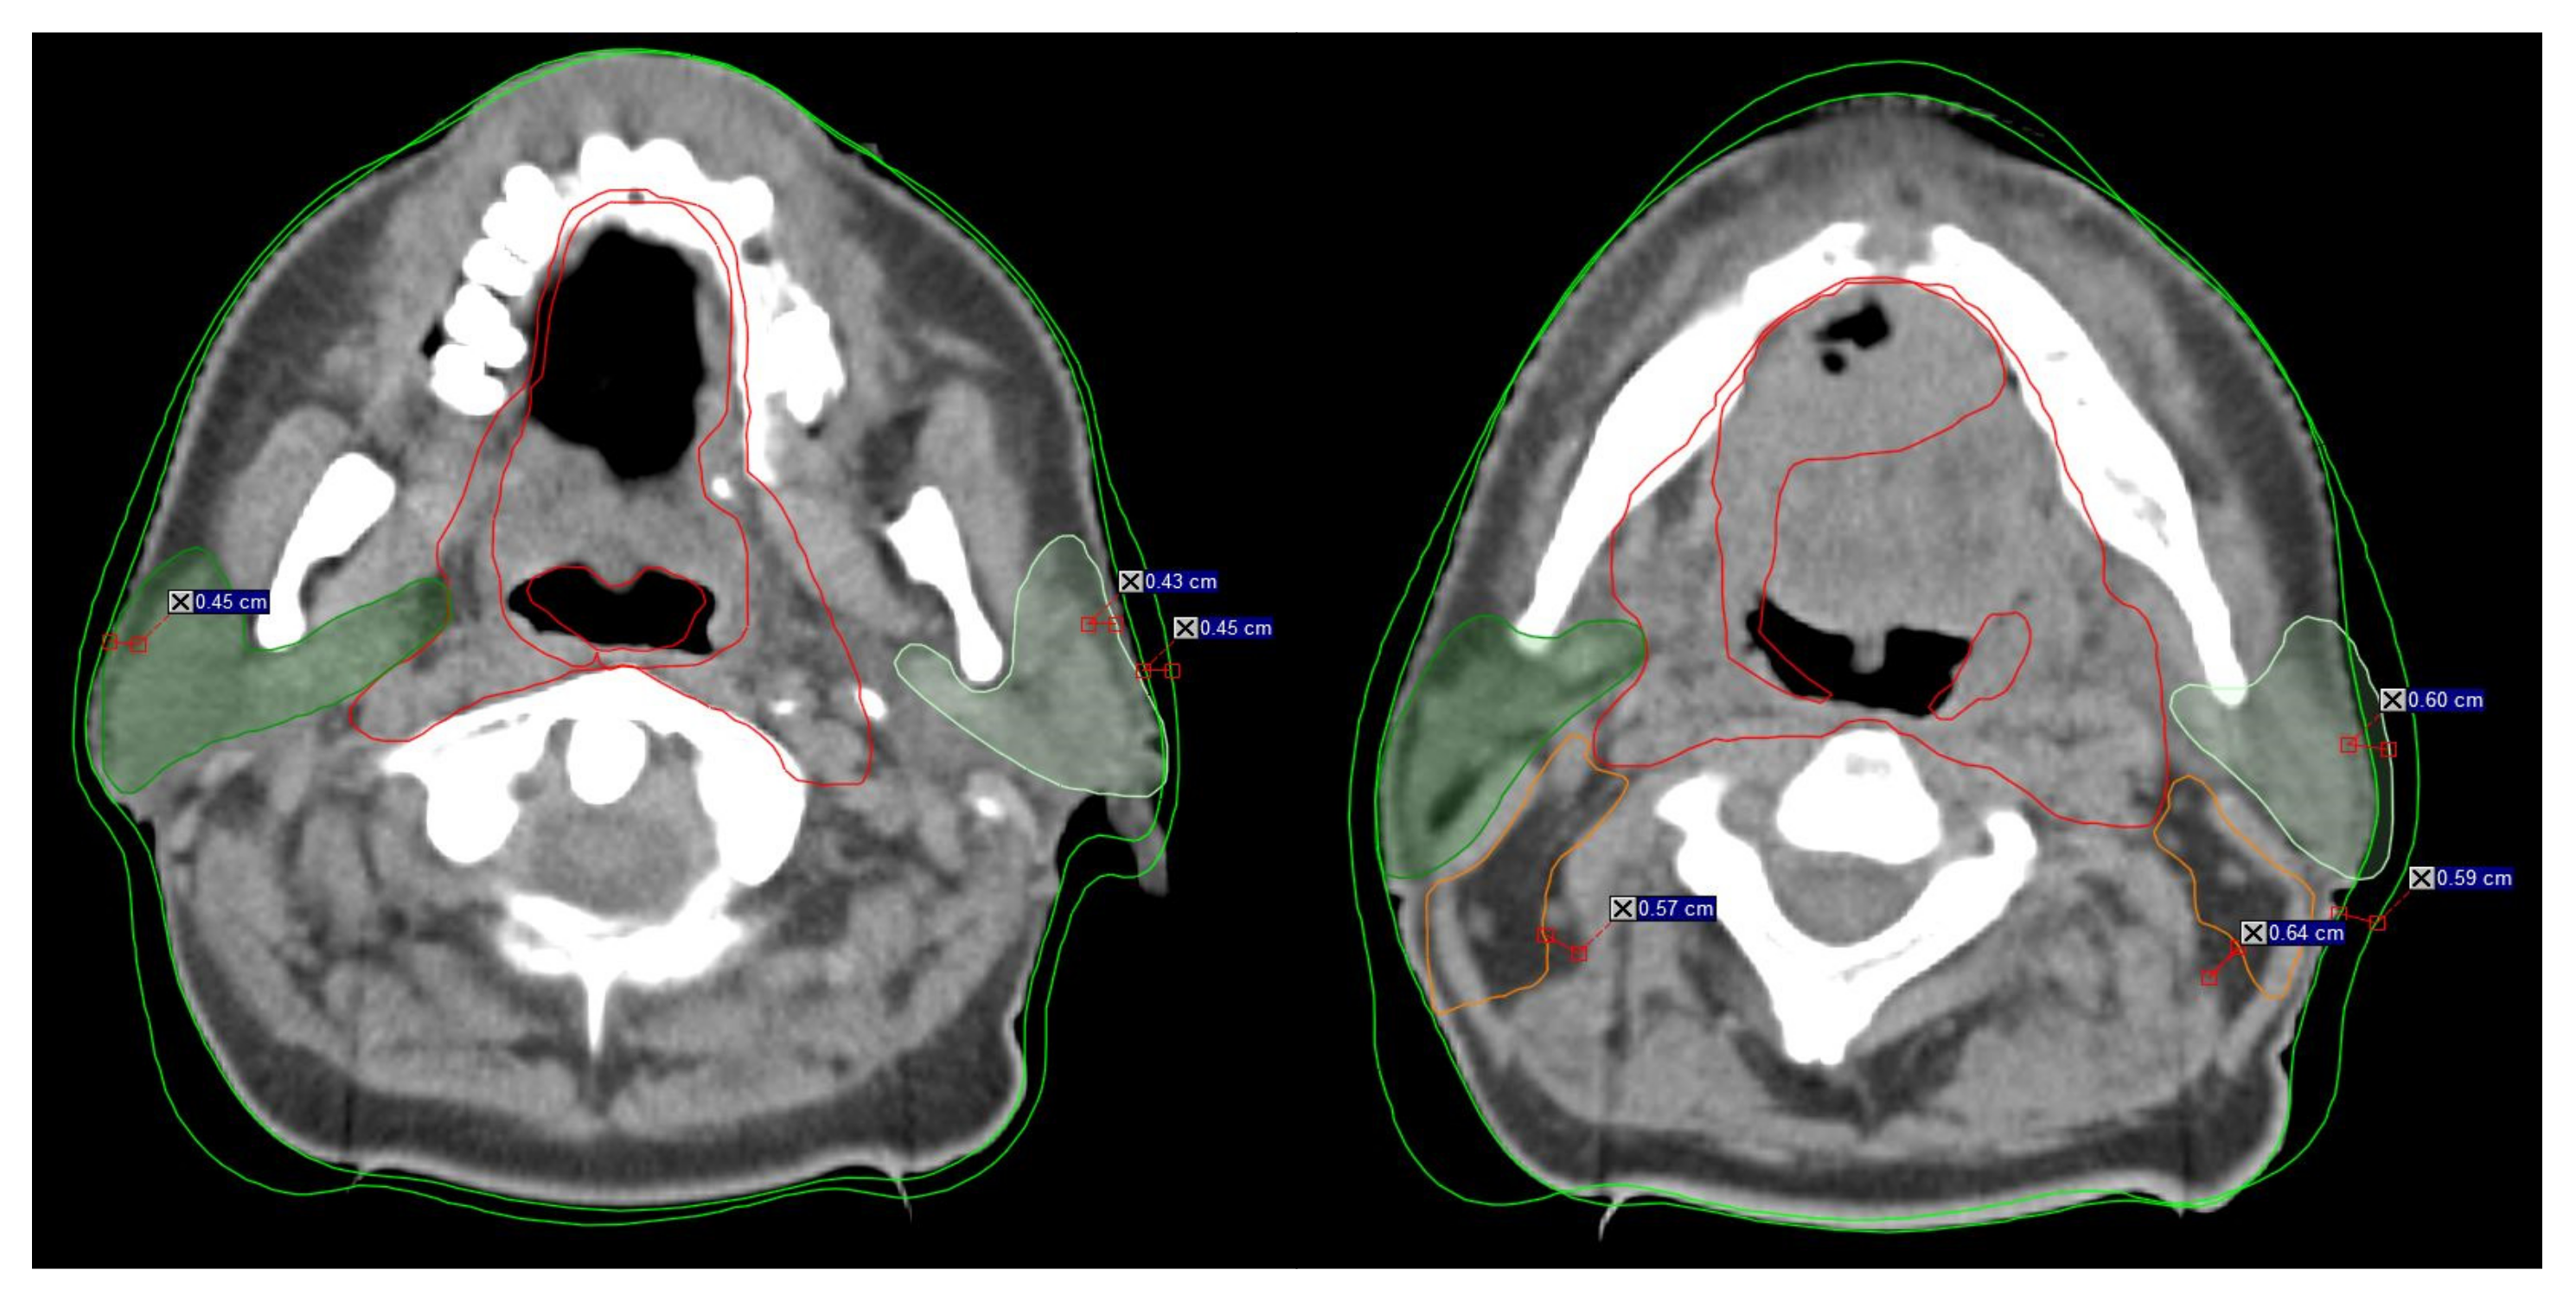

Figure 1.

Example of the rapidly changing anatomy during head neck radiotherapy from treatment initiation to replanning. Visible changes >3 mm in the anatomy during RT indicate inclusion for B-ART. The distance mark on the scans represents the anatomy changes between initial CT (iCT) and replanning (rCT). Dark green indicates the right parotid gland, and light green indicates the left parotid gland. Red indicates CTV1, orange indicated CTV2, and green indicates the external contour (B-body).

Careful analysis of the anatomical changes evidenced on IGRT-based imaging can potentially help us to predict subsequent changes in the primary tumor, lymph nodes, parotid glands, and body volume during radiotherapy. The B-ART protocol can therefore help us to identify the patients who most likely to benefit from replanning. According to the protocol criteria, if the difference between the patient’s external (body) contour on the MVCT and the iCT is greater than 3 mm on at least three to four scans (3-mm slices) on any of the treatment volumes (CTV, PTV, or PG), the RTT must notify the radiation oncologist, who must then confirm that the patient meets the protocol criteria and schedule a new CT image for replanning (Table 2, Figure 1).

During a typical course of radiotherapy in patients with HN cancer, the average volume reduction in the PGs is 26% [3,4,6,8,11,13,18,21,24,26,32,40,41]. We grouped the PG volume changes into five groups according to the percentage change (Table 6). Most of the patients (n = 30; 36.6%) experienced a volume reduction ≥30%. The greatest absolute and percentage reductions in PG volume were 6.31 cc (20.9%) and 5.98 cc (20.5%) for the right and left PGs, respectively. These results are consistent with the findings obtained by other researchers [10,13,26]. In patients with OPC, the largest percentage volume reductions in the right and left iPG were 27% (7.2 cc) and 25% (6.0 cc), respectively (Figure 1), indicating that >39% of these patients would require replanning, and should therefore be included in the high-risk group. By contrast, Brown et al., estimated that only 2% of OPC patients versus up to 67% of node-positive NPC patients (stage N3) would require replanning [1], leading them to conclude that some patients with other HN tumors (e.g., OPC) may be considered high risk depending on the tumor characteristics. However, given the small number of patients who underwent ART in that study, those findings should be interpreted cautiously. Nevertheless, as our data show, ART has a profound impact on HN patients in general, not only on high-risk groups such as those with OPC or NPC with advanced nodal disease. Our findings indicate that replanning during IMRT is essential for all HN patients undergoing CRT; this same conclusion applies to the PORT group, although the results were not quite as strong.